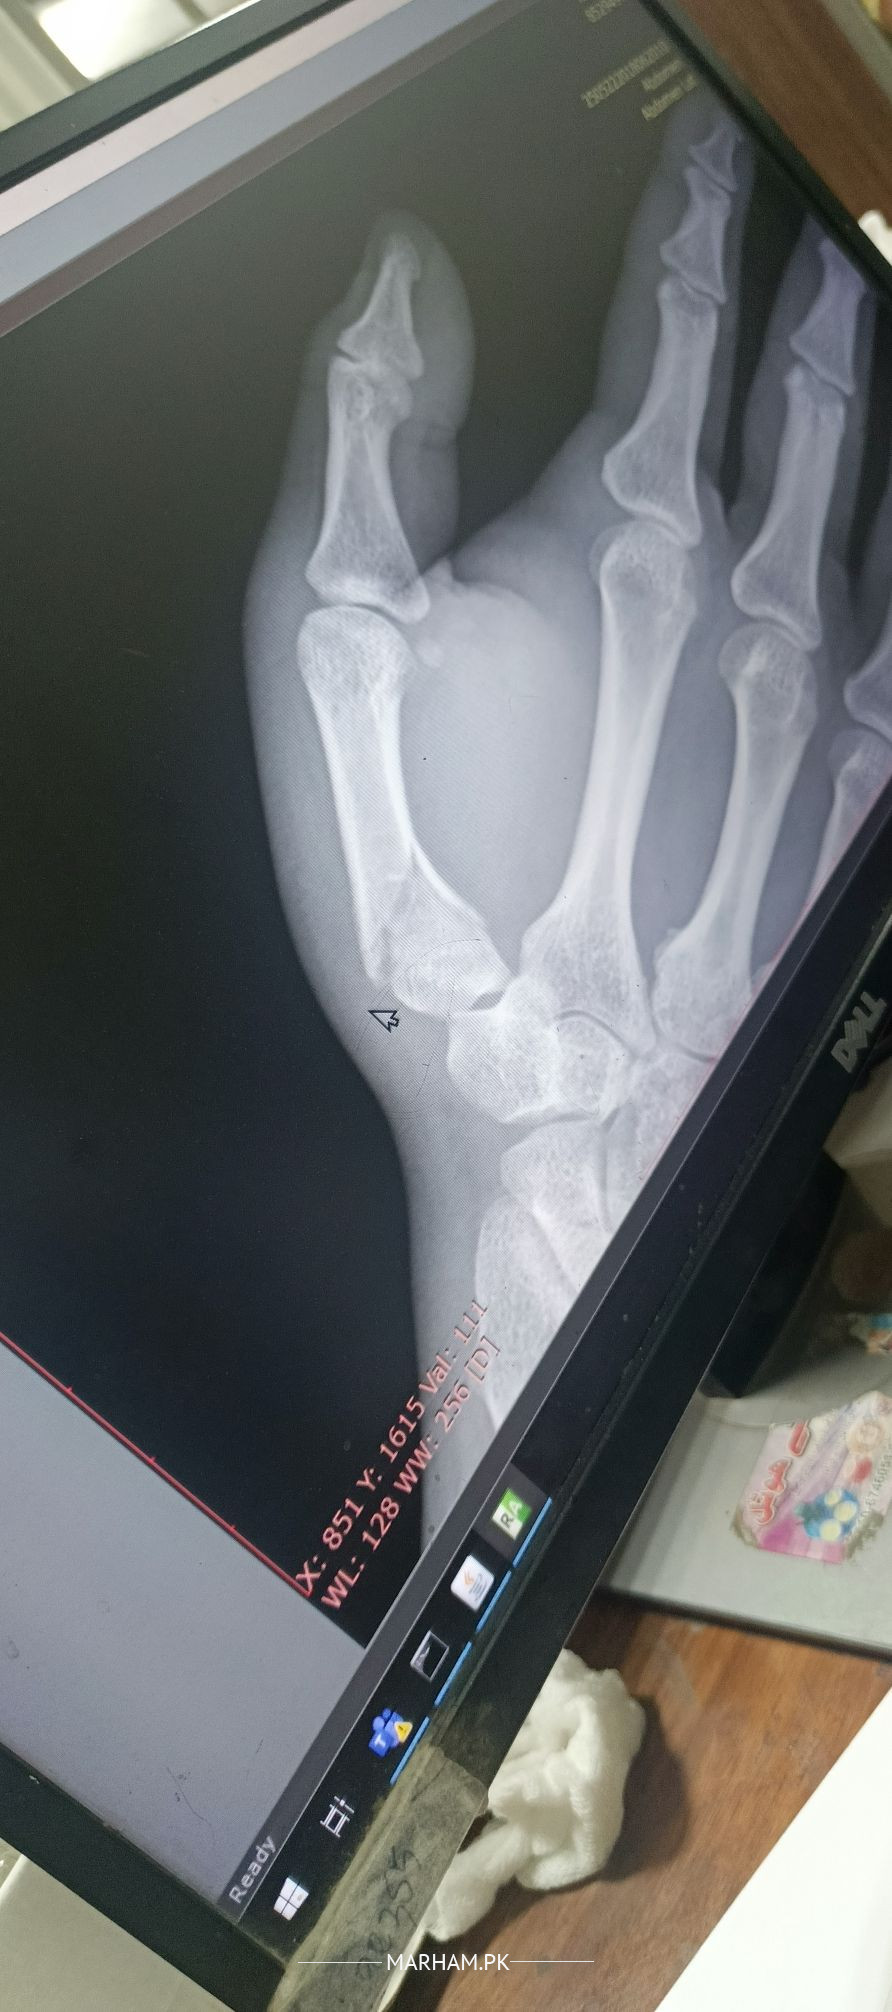

assalam u alaikum mera thumb 17 days pehle thoot gaya tha oer mene 15 days k leye plaster/cast lagaya leken mene ehtiat nahi ki per mene aj x ray leya to thumb ki halat wese ki wese hai. guide kare please kia karna chaheye

please apply pop again and keep it for 30 days.

Your thumb must be incorporated in the POP.

fracture is still not displaced.

it has acceptable position, However need to tailor the treatment plan according to patient need and dominance of hnad, profession etc nd I might fear you may have associated carple bone fracture.. scaphoid..?